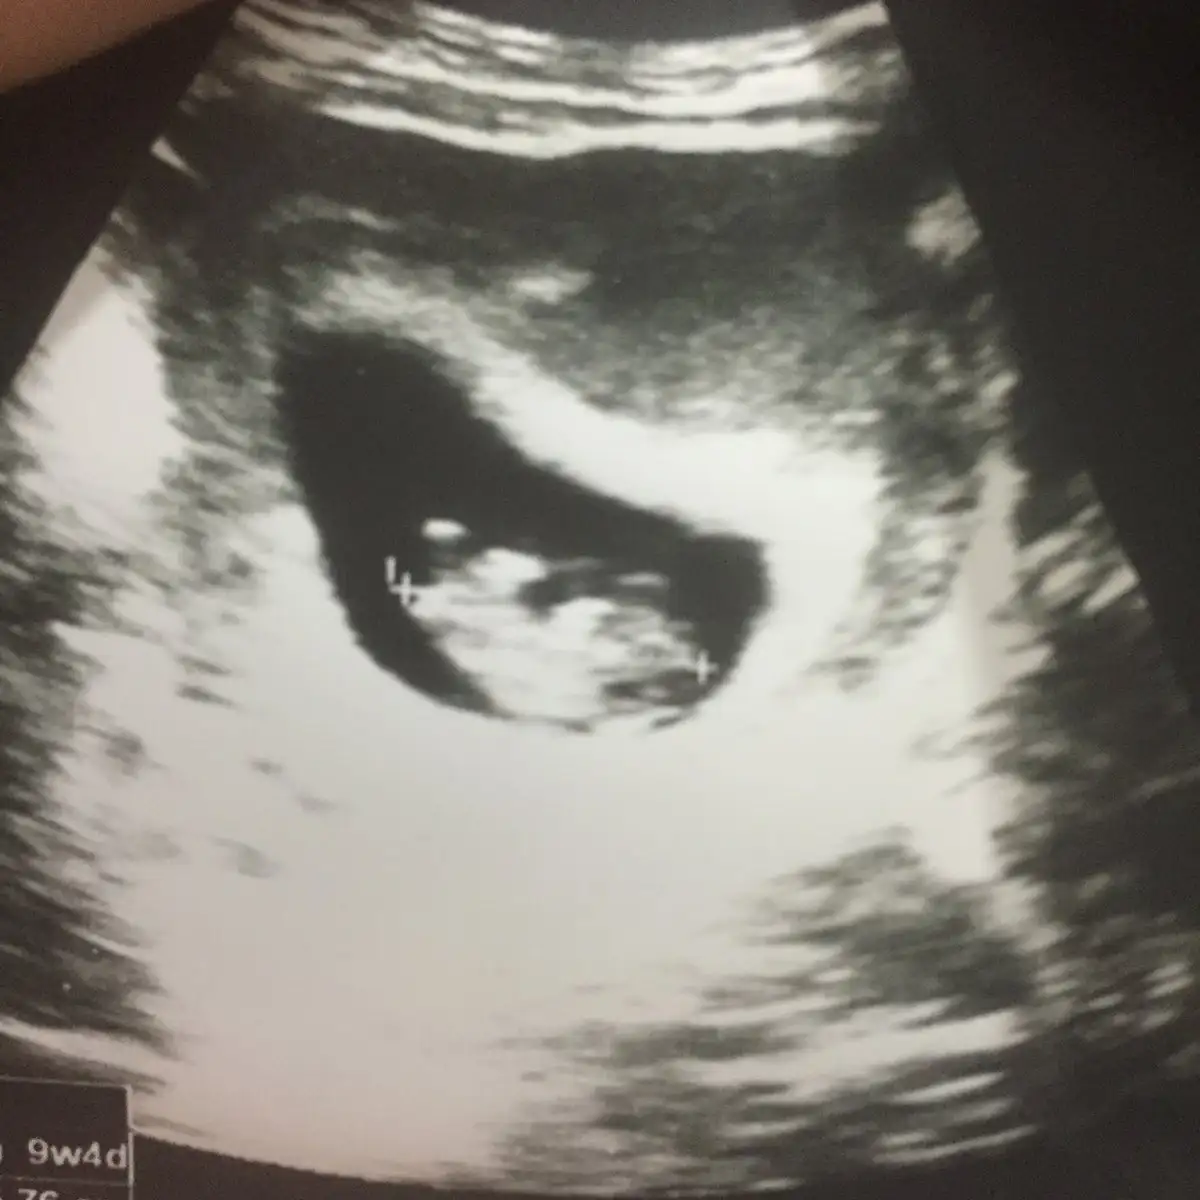

Ramzi Teorisi ve cinsiyet tahmini ( tutma olasılığı %85 miş )

Kızlar tahminlerinizi bekliyorum 7+5

Ramzi teorisine göre ( bilimsel bir araştırma sonucuymuş ve %85 doğruluğu varmış). İlk 6-8 haftalık ultrason görüntüsüne göre bebeğin kesenin içersinde soldan ya da sağdan girişine göre cinsiyet tahmini yapılıyor. Bilimsel olunca tecrübeli annelerimiz yada anne adaylarımızdan yardım istiyoruz. Doğruluğu var mı öğrenmek adına :) Bizleri aydınlatırsanız çok seviniriz. bu teorieye göre;

Vajinal muayeneyle bakıldıysa eğer;

Sağdan girmiş gözüküyosa aslında solmuş ve ERKEK,

Soldan girmiş gözüküyosa aslında sağmış ve KIZ ,

Karından bakıldıysa eğer,

Soldan girmiş gözüküyosa gerçektede solmuş ve ERKEK,

Sağdan girmiş gözüküyosa gerçekte de sağmış ve KIZ,